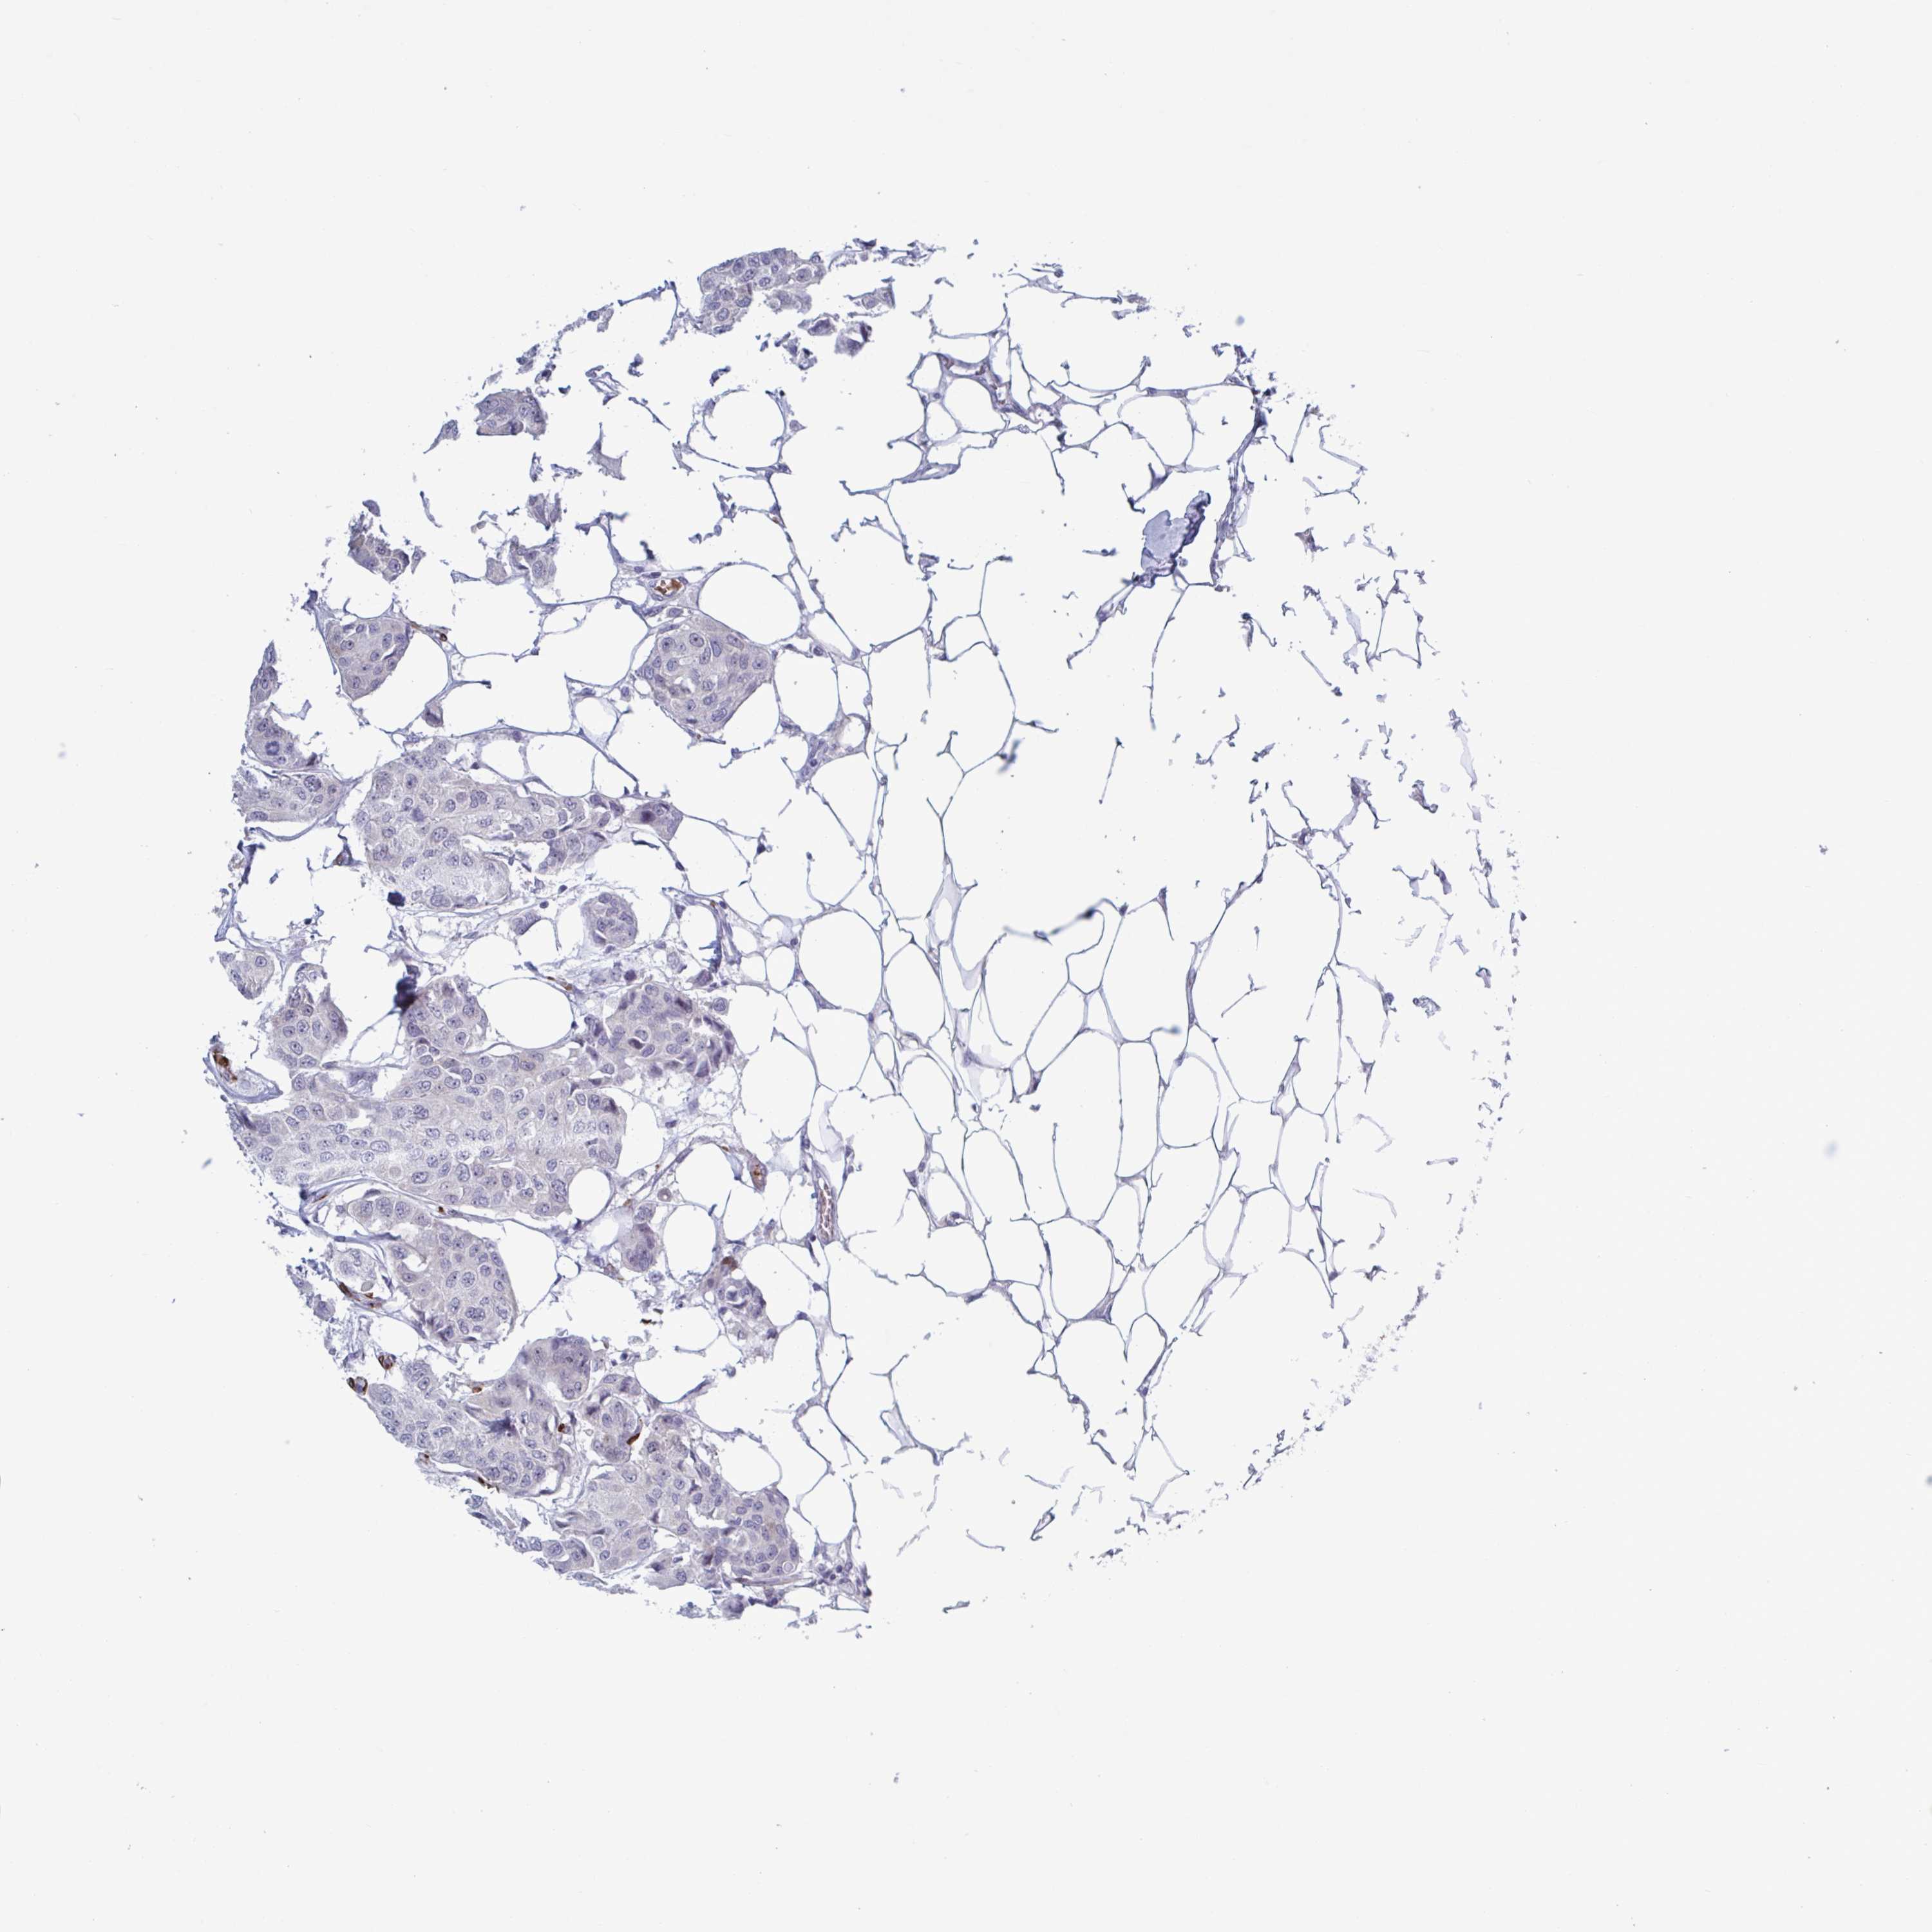

CANCER BREAST CANCER Show tissue menu

BRCA TCGA BRCA VALIDATION PROTEIN EXPRESSION